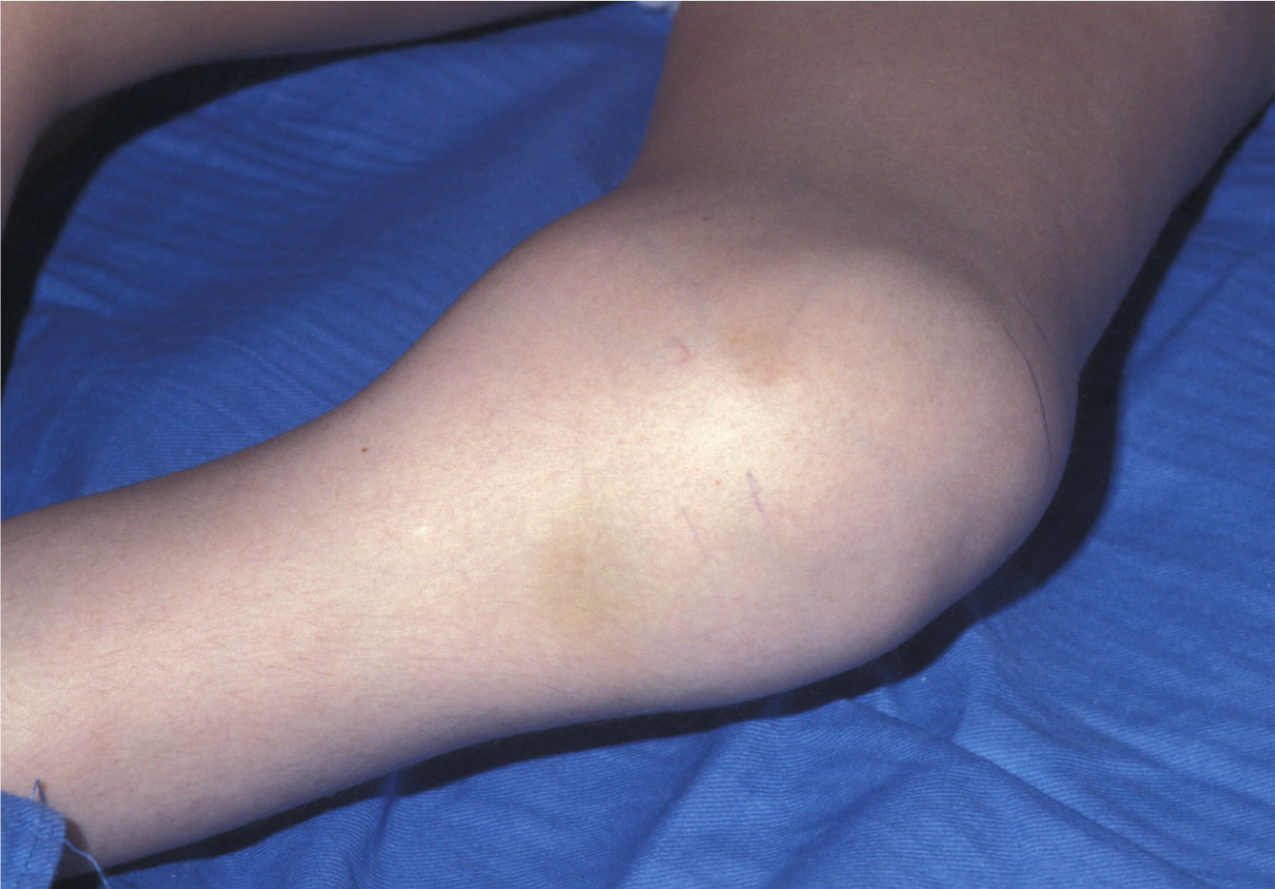

what is shown here?

Injury

Man hit with tennis ball

Severe injury for being hit with tennis ball

haemophilia